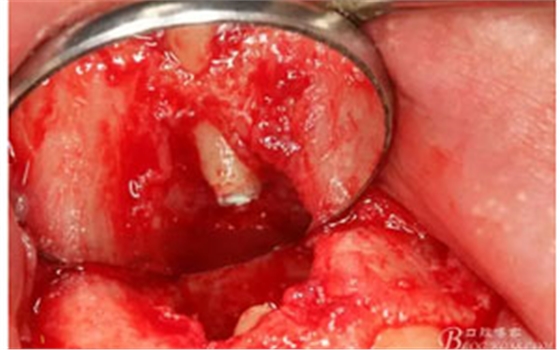

圖8.從垂直切口和水平切口的連接處翻瓣。發(fā)現(xiàn)11和12之間的骨壁有缺損。

圖9.翻開角形瓣后,有骨壁缺損,囊壁有穿孔,這就是溢膿的竇道出口。

圖10。用骨膜剝離器沿著骨壁、緩慢逐漸剝離囊壁。